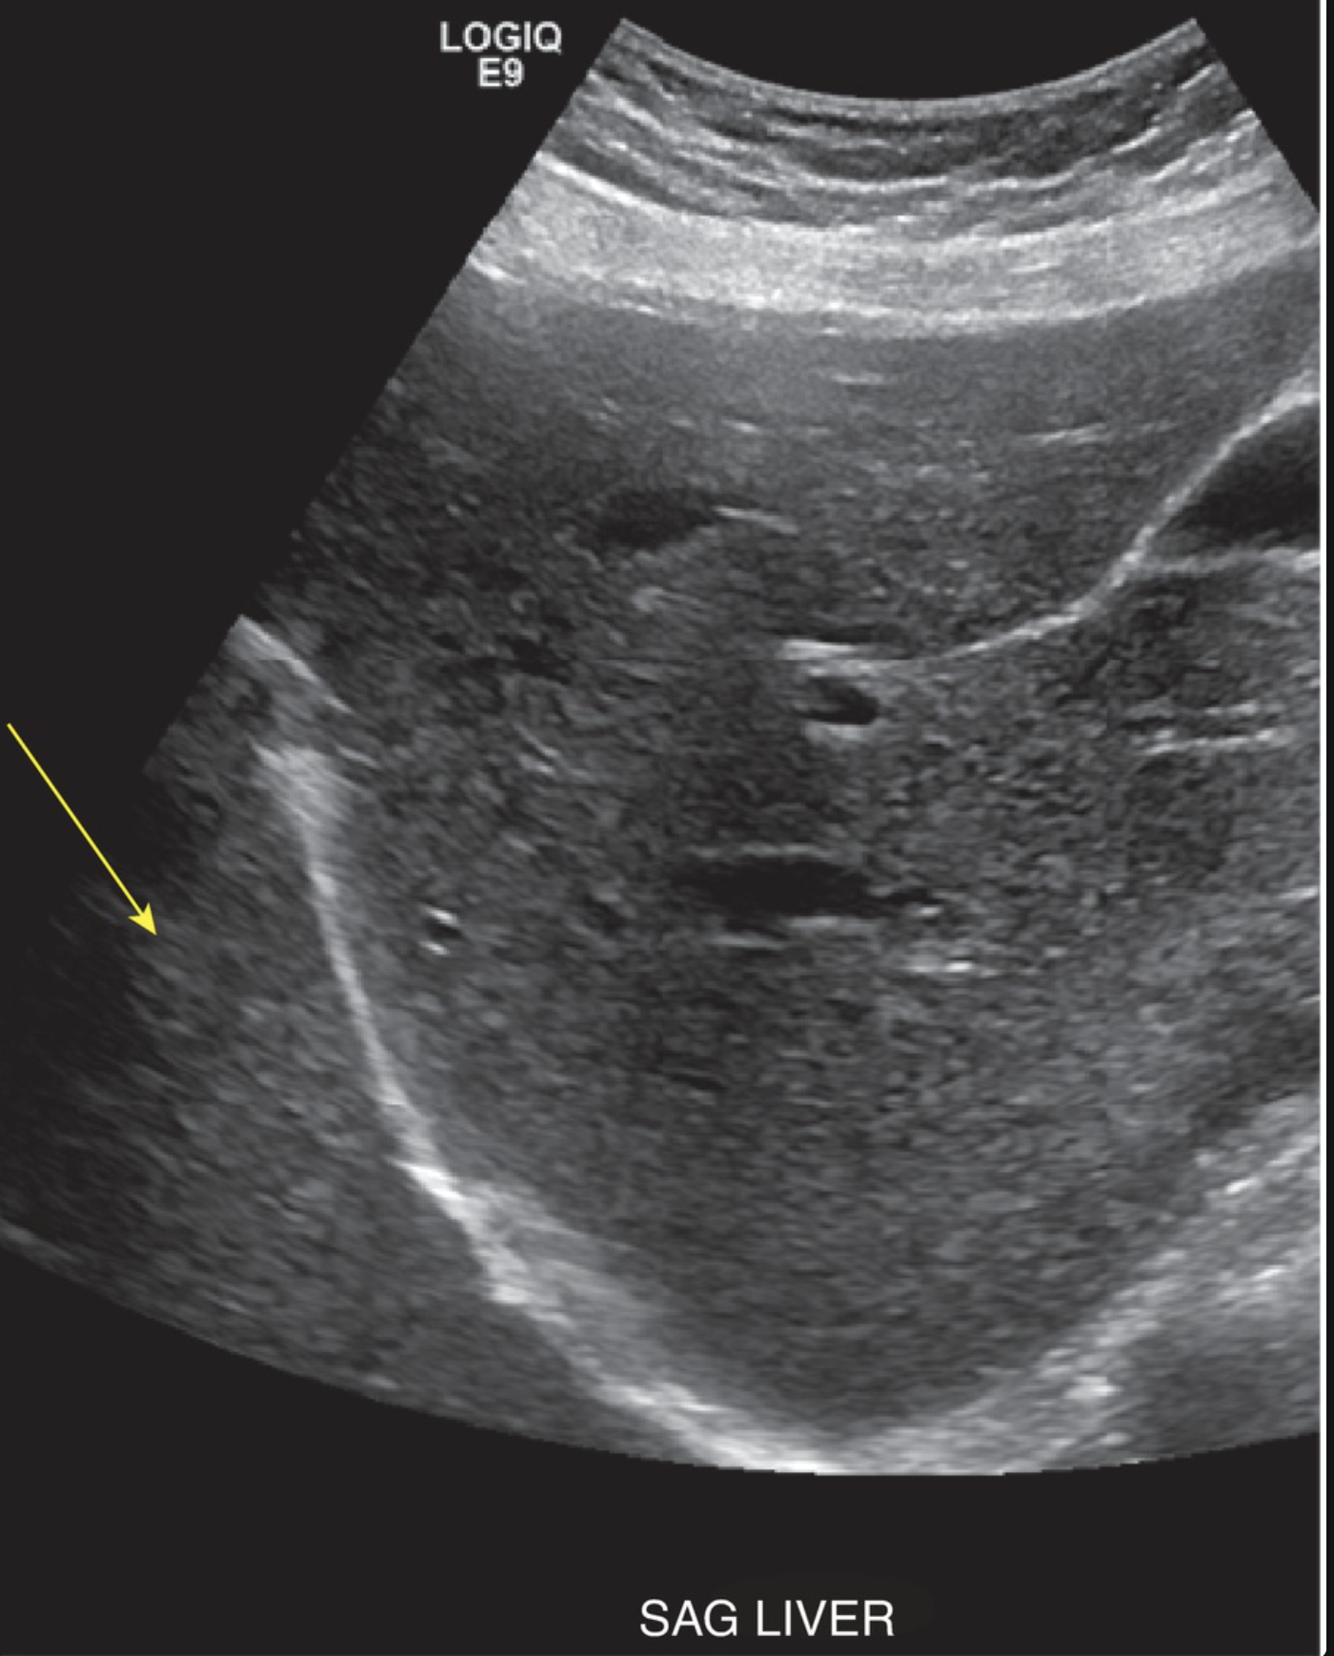

Which phenomenon is responsible for the following US artifact?